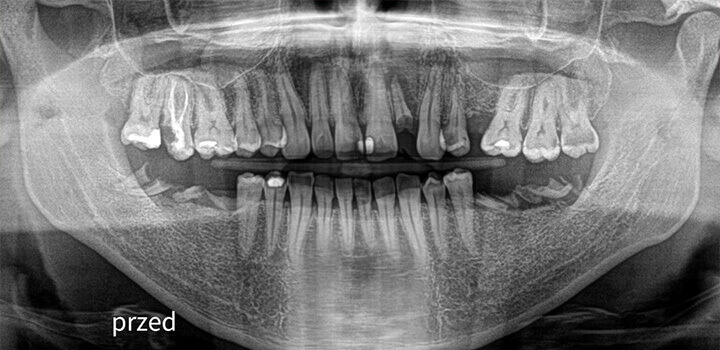

Efekty, które mówią same za siebie